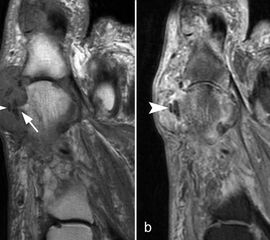

Typische Gichtmanifestation an der Großzehe mit Tophusstachel (Pfeil) und großem Tophus, in welchem Uratablagerungen identifiziert werden können (Pfeilspitze). T1-gewichtete Sequenz vor (a) und nach (b) Kontrastmittelgabe, letztere mit Fettsuppression.

Abbildung 15

Dies erst recht, wenn diese Arthritis am Großzehen­grundgelenk auftritt (Abb. 15). In diesen Fällen sollte man den Verdacht auch dann aufrechterhalten, wenn die MRT nur eine unspezifische Entzündung zeigt und die Harnsäurewerte, die starken Schwankungen unterliegen können, nicht erhöht sind.

Spezifische MR Befunde finden sich erst bei der chronischen Gicht, wenn sich in T2 sehr signalarme Kristallablagerungen und Gicht-Tophi bilden. Letztere führen dann häufig zu den aus der Röntgendiagnostik bekannten gelenkfernen Erosionen.

Abbildung 15: Typische Gichtmanifestation an der Großzehe mit Tophusstachel (Pfeil) und großem Tophus, in welchem Uratablagerungen identifiziert werden können (Pfeilspitze). T1-gewichtete Sequenz vor (a) und nach (b) Kontrastmittelgabe, letztere mit Fettsuppression.